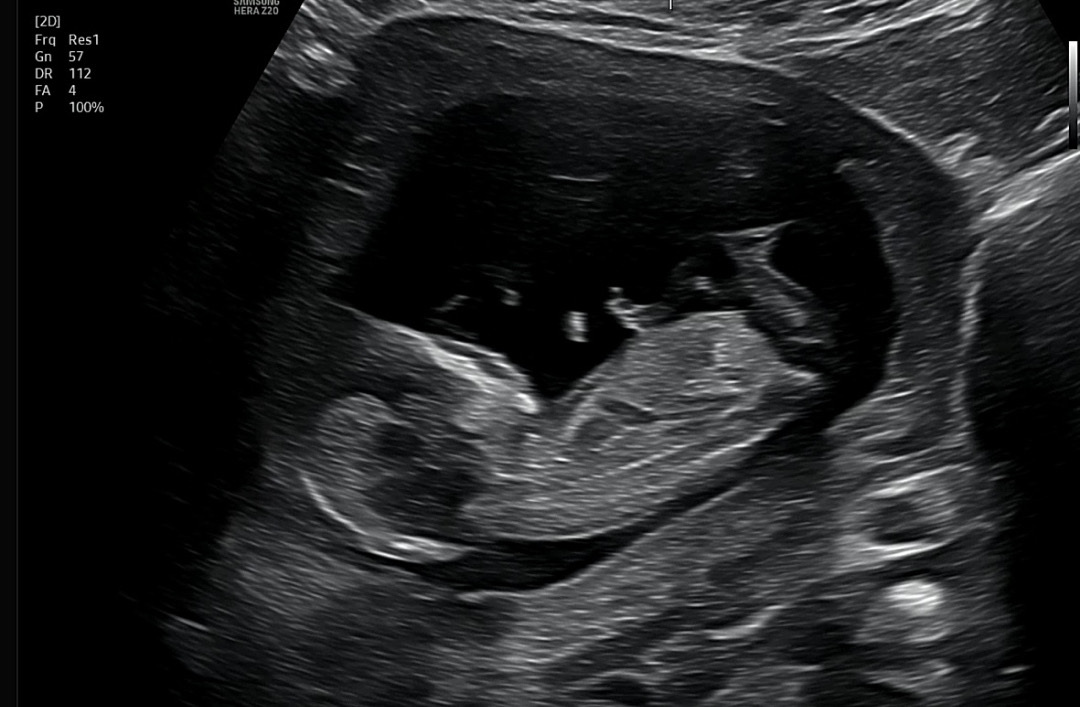

12주 5일 각도법 봐주세요!

예측 부탁드립니다:)